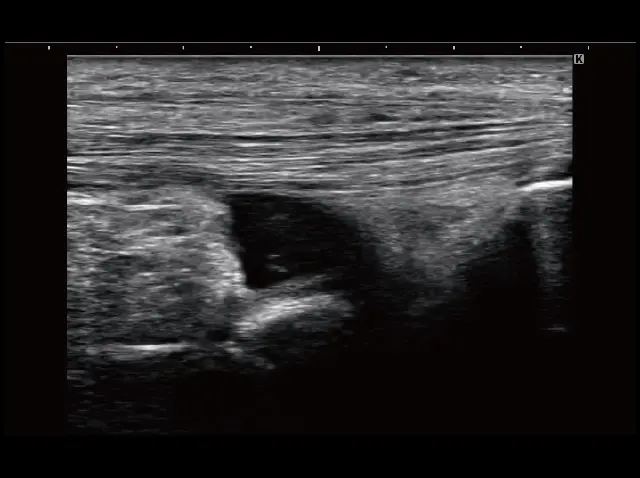

イメージギャラリー

イメージ画像を表示する